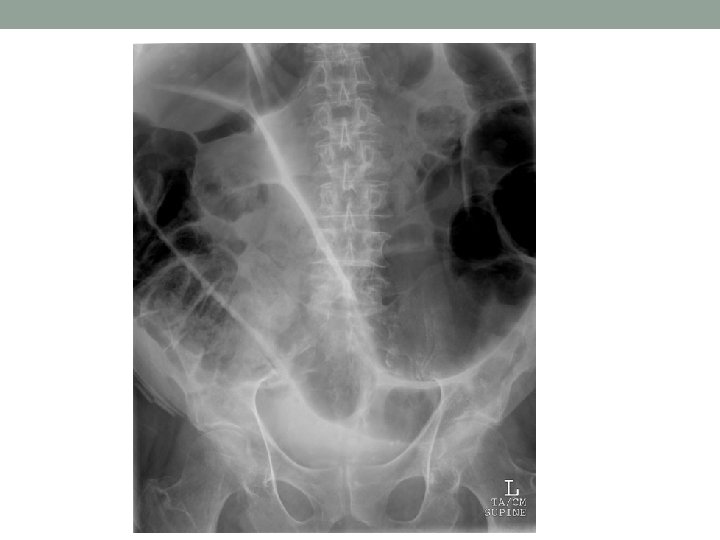

AXR Demographics/ Type of XR Black: dilated loops / Air • Small = central, valvulae conniventes • Large = Peripheral, Haustrae White: Calcification • Renal stones/ Gallstones • Foreign Bodies • Bone Grey: soft tissue • • Liver, spleen, pancreas, gall bladder, ovary, uterus Enlargement, calcification Abdominal wall muscles, hernias Stool Re-review and summarise

Air in Abdomen • Post-op/ Post-ERCP • Perforation • Cholangitis • Abscess • Gallstone Ileus